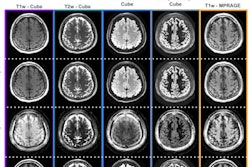

Of these patients, they focused on 132 who underwent dynamic contrast-enhanced (DCE) imaging and quantitative susceptibility mapping (QSM) between January 2013 and May 2020 at Konkuk University Medical Center. Choroid plexus volume was automatically segmented using 3D T1-weighted sequences.